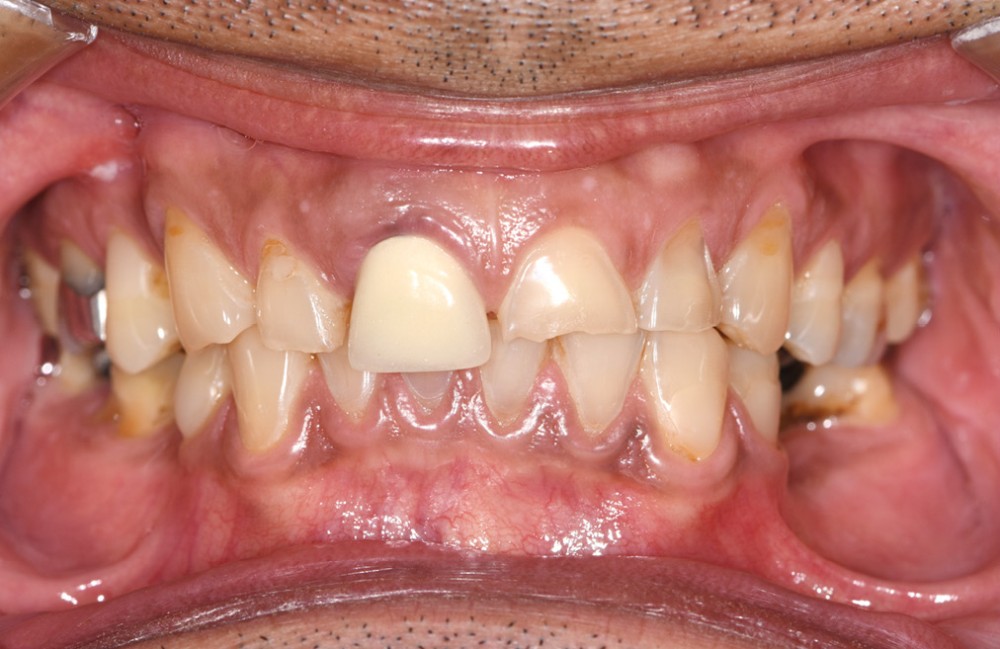

L’étiologie de cette usure est multifactorielle, revêtant une composante de type attrition (usure par contact dento-

dentaire), une composante abrasive avec un brossage traumatique et, en dernier lieu, une légère composante tribo-érosive de par une pratique importante de sport avec gel et boisson acide (fig. 1-4) [1].